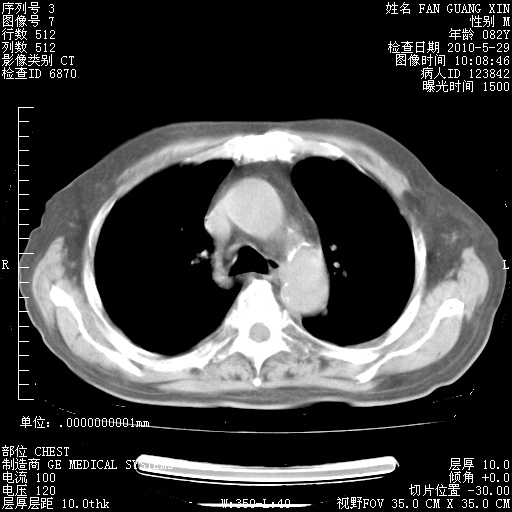

再治疗10天后的肺部CT

再治疗10天后的肺部CT 纵膈窗